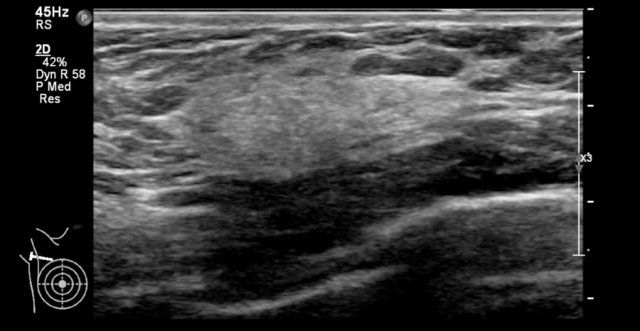

The images are of a 50-year-old woman who presented with palpable masses in the axilla, that represented round enlarged hypoechoic lymph nodes.

Subsequently there was an ultrasound examination of the breast, which revealed a small non-palpable hypoechoic irregular cancer.